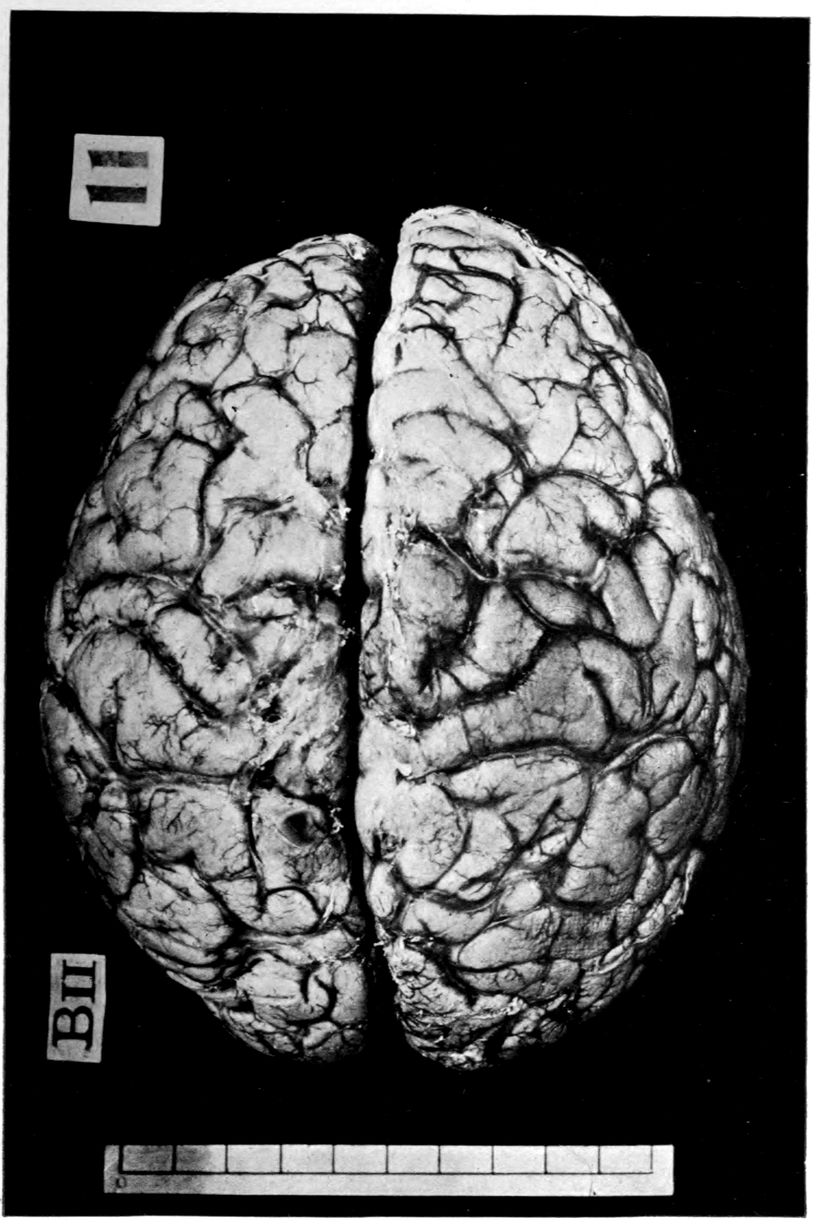

39Crown bald, with a slight fuzzy growth of short hairs. Scalp slightly adherent to calvarium; latter of usual thickness but denser than normal. Dura adherent to calvarium in region of vertex; dura not remarkable. Sinuses normal. Arachnoid villi moderately developed. Pia mater a trifle thickened and rather evenly throughout the cerebral portion. Linear sulcal markings are remarkable for their absence. The wall of the cerebellomedullary cisterna is thick and opaque. The most prominent pial thickenings are over the cerebellum. These are linear or may show feathery out-growths and are seated over the sulci, particularly in the neighborhood of the fissure and about the great cerebellar notch. They correspond fairly well with the focal variation in consistence of underlying tissues noted below.

Brain weight, 1265 grams. Consistence somewhat increased throughout and somewhat evenly increased. The prefrontal region shows the maximal increase of consistence but the remainder of the frontal region and corresponding occipital region are much firmer than normal. The two superior temporal gyri appear to be firmer than adjacent gyri and are possibly slightly diminished in superficial diameter. The hippocampal gyri are fairly firm. The substance on section is a trifle more moist than normal. The gray and white matter cut quite evenly. Diminution in depth of gray matter, if existent, could not be demonstrated. The ventricles show a moderate sanding throughout, best marked in the fourth ventricle. The basal ganglia are not remarkable except for the development of numerous dilated perivascular spaces about the lenticulostriate vessels. The pons is atrophic, but more so on the right side. The pons, like the prefrontal cortex, shows on section a distinct increase of consistence immediately beneath the pia mater. The white bands of the pons on section are distinctly firmer than the intervening substance. The olives are of equal consistence. Weight of cerebellum, pons, and medulla, 155 grams. The cerebellum shows an obvious atrophic and gliotic process of a symmetrical character. The superior surface, including both vermis and hemispheres, shows a consistence above normal and general reduction of the depth measured from the white matter. The reduction in depth gives rise to a visible depression as compared with tissue posterior to the postclival sulci. The lobus cacuminis, though slightly raised from the surrounding lobes, is equally firm, if not firmer. The superior and inferior surfaces show practically an equal increase of consistence. The dentate nuclei are not especially increased in consistence. The flocculi are reduced in size about one-third.